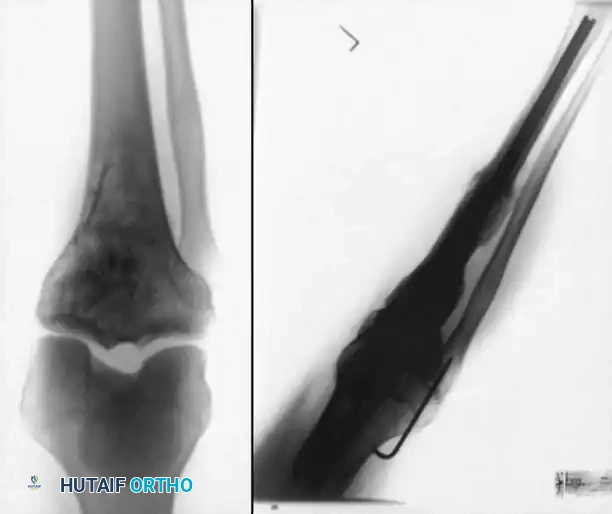

Clinical Pearl: Short Locked Nails

Cheng and Gross described the use of short, locked intramedullary nails designed specifically for knee fusions. These devices avoid the need for a secondary proximal incision (required for long antegrade nails) and bypass the bulkiness of double-plating techniques, offering an excellent alternative for patients with adequate diaphyseal bone stock.

3. Plate Fixation and Adjunctive Techniques

While external fixation and IM nailing are the most common techniques, internal fixation using heavy-duty plates is a viable alternative, particularly when the medullary canal is obstructed (e.g., retained hardware, severe deformity) or when rotational control is paramount.

Technique:

* Anterior Plating: A broad, heavy-duty dynamic compression plate (DCP) or locking compression plate (LCP) can be contoured to the anterior surface of the femur and tibia. This acts as a tension band when the knee is subjected to flexion forces during weight-bearing.

- Dual Plating: For enhanced biomechanical stability, orthogonal or dual parallel plating (medial and lateral) can be employed. This is particularly useful in cases of massive segmental bone loss where structural allografts or massive autogenous grafts (e.g., vascularized fibula) are utilized to bridge the defect.